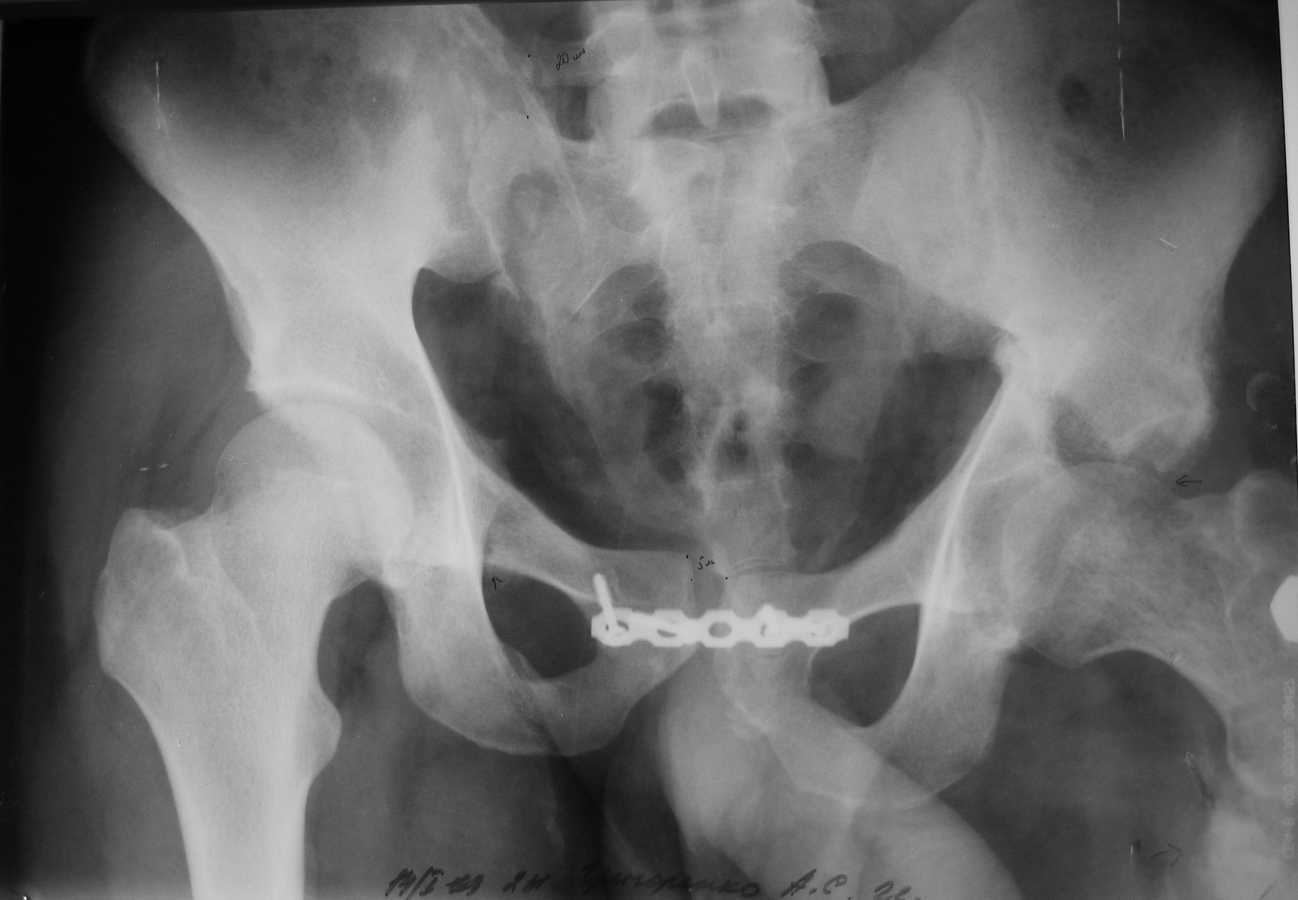

Также имеется травматическая деформация таза с трансвертлужным переломом на стороне дефекта. Планируется замещение дефекта транспортом кости.Хотелось бы услышать ваши советы по поводу оптимальной компоновки АВФ (стержневой, спице-стержневой), есть ли необходимость в дополнительной фиксации за кости таза?

А вот таз - отдельная проблема, вернее, две - краниальное смещение правой половины таза, и нелеченный высокий поперечный перелом вертлужной впадины. Как Вы намереваетесь решать эти проблемы?

Хотел-бы поддержать точку зрения уважаемого А.Н. Челнокова - больших проблем с бедром тут не должно быть, ситуация с тазом куда более серьезная. Судя по крестцово-подвздошному, там более 5 см смещение.

Насчет таза там большие упущения, пластина на симфизе - доказательство отсутствия знания методики лечения переломов таза и ацетабулум. Хотя бы скелетным вытяжением можно было приблизить правую половину таза.

Разрыв крестцово-подвздошного сочленения и поперечный перелом вертлужной впадины являются показанием для оперативного лечения.

Для планирования восстановления таза и ацетабулум, если у вас имеется возможности и желание, тогда надо сделать все стандартные рентгенологические исследования по Judet для ацетабулума, Inlet Outlet снимки для таза и Компьютерная Томография.